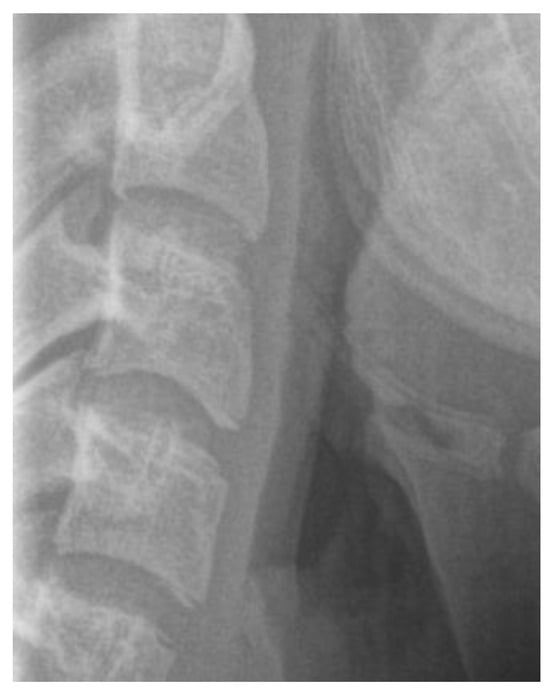

3.3.2. Cervical Vertebrae Radiography